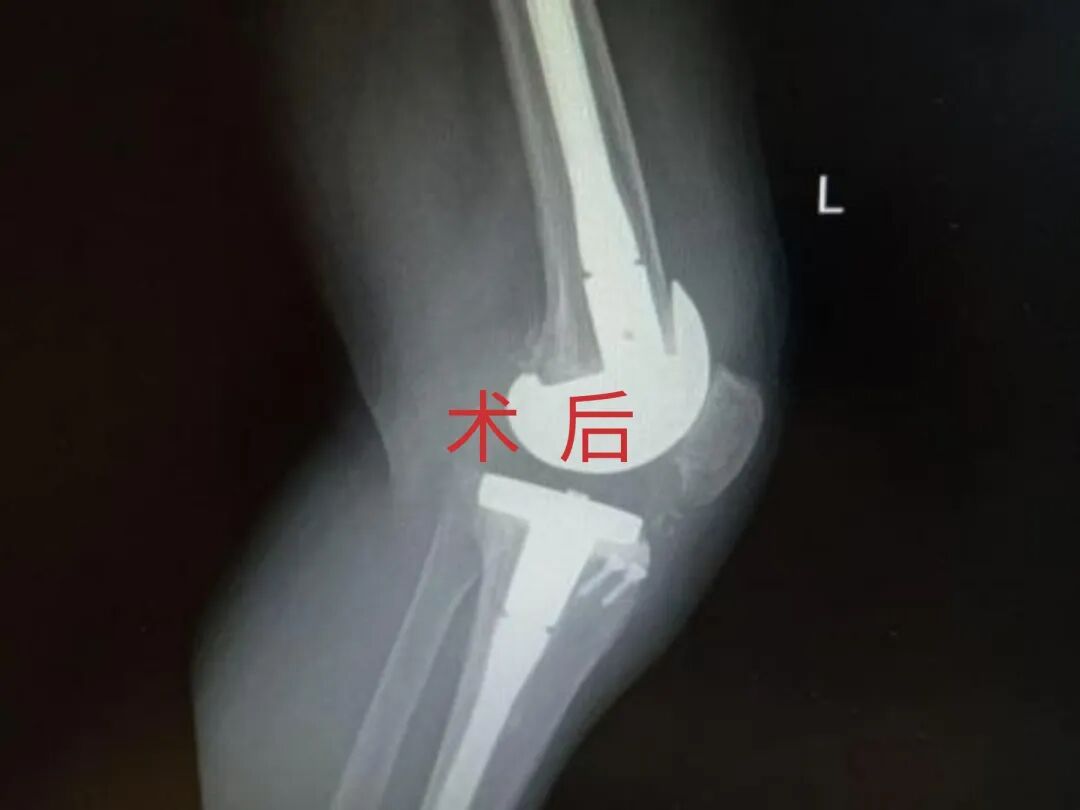

2025年11月1日,由遵义市医学会手外科分会主办、遵义市第二城市医疗集团(贵州航天医院)承办的遵义市医学会手外科分会学术交流会暨贵州省继续医学教育项目《急诊手外伤治疗临床研究新进展专题研讨班》在贵州航天医院成功举办,汇聚了遵义市手外科领域专家及基层医疗骨干,通过专题研讨与临床经验分享,共探急诊手外伤诊疗新进展。 会议特邀遵义市医学会手外科分会主任委员金文虎教授,遵义市医学会手外科分会副主任委员张子阳教授,遵义市医学会手外科分会常务委员杨绍浦教授,贵州航天医院陈明勇教授、赵兴东教授等遵义市手外伤专家进行交流分享;贵州航天医院党委委员、副院长彭亮参加会议并致辞,贵州航天医院骨科医务人员,遵义市第二城市医疗集团成员单位及红花岗区、绥阳县、桐梓县等区县医疗机构手外伤骨干参与。 贵州航天医院党委委员、副院长彭亮致辞 学术交流 本次学术交流以“急诊手外伤治疗临床研究新进展”为主题,通过理论授课与临床案例结合,共同探讨急诊手外伤临床诊疗全链条诊疗策略、关键技术、临床研究新进展,促进规范化诊疗技术向基层下沉,助力提升区域手外伤应急处置与修复能力。 贵州航天医院赵兴东教授分享《急诊手外伤的诊断与治疗原则》 贵州航天医院陈明勇教授分享《开放性骨折的治疗原则》 贵州航天医院张军教授分享《甲沟炎Winograd手术的临床应用》 贵州航天医院赵兴东教授分享《手部常见的皮肤缺损及治疗原则》 贵州航天医院张艳金教授分享《开放性骨折的清创术》 贵州航天医院冷家雄教授分享《下肢创面修复的常用皮瓣之股前外侧皮瓣》 贵州航天医院邬夏荣教授分享《踝关节慢性不稳的诊治》 贵州航天医院卢懿明教授分享《掌骨骨折》 贵州航天医院张艳金教授分享《手部肌腱的解剖与修复方法》 本次研讨班为遵义市手外科领域医务人员提供了深度交流契机,强化了医疗机构间的协作网络,进一步推动学科创新与临床实践融合,为健康遵义建设注入新动能。 贵州航天医院骨科专家简介 陈明勇 骨一科主任,副主任医师 临床擅长:从事创伤骨科工作约20年,对骨缺损、骨不连、骨肿瘤、肢体畸形等的肢体矫形重建及功能重建,慢性化脓性骨髓炎的根治治疗、糖尿病足的保肢治疗、快速康复理念(ERAS)下的老年骨折的诊治,四肢复杂骨折的诊治,四肢骨折等微创手术治疗具有丰富的临床经验。 2004年毕业于遵义医学院临床专业,曾在中国人民解放军总医院、广西医科大学第一附属医院、上海第六人民医院骨科进修。中国中西医结合学会骨伤科专业委员会横向骨搬移治疗糖尿病足及微血管网再生学组首届委员,遵义市医学会创伤分会常务委员。 瞿 晖 骨科党支部书记,骨二科主任,副主任医师 临床擅长:对骨科的常见病、关节外科、脊柱外科及运动医学疾病的诊治具有丰富的临床经验,熟练掌握骨科手术操作技术。 毕业于遵义医学院临床医学系,2005年前往广州中山大学第一附院骨显微医学部进修学习,2011年前往成都华西医院进修学习,并多次在省内外学习骨科相关知识,是中华医学会骨科分会会员。 赵小锋 中共党员,骨二科副主任,副主任医师 临床擅长:从事骨科临床工作11年,对骨科常见病、多发病诊疗有较为丰富的临床经验,擅长脊柱相关疾病诊断及治疗,尤其是颈、腰、腿疼痛疾病诊断及治疗,擅长胸腰椎骨折微创经皮穿刺内固定术、经皮穿刺椎体成形术、经皮穿刺脊柱内镜下腰椎间盘摘除术、单纯开创腰椎间盘摘除术、腰椎滑脱复位椎间植骨椎融合内固定术、腰椎管狭窄减压融合内固定术及人工髋、膝关节置换术等。 2012年毕业于遵义医学院外科学专业硕士研究生,2019年参加“遵义市115医学人才精英计划”于上海交通大学第一附属医院培训学习,2023年于北京大学第三人民医院脊柱外科进修学习,曾获得遵义市优秀医师荣誉称号。 遵义市手外科第一届委员,遵义市医学会创伤分会第一届委员,遵义市医学会创伤分会第二届委员,贵州省康复医学会第三届脊柱脊髓专业会委员,遵义市医学会烧伤与整形外科学分会委员,发表论文5篇,其中国家级核心期刊1篇,SCI论文1篇,主持市级课题1项并结题,参与市级课题2项。 赵兴东 骨科主任医师 临床擅长:擅长骨科的常见病及各种创伤、四肢骨折创伤修复、骨感染、手足疾病的诊治和手足体表畸形的矫形整复,熟练掌握骨科四肢骨病及创伤的手术操作技术,尤其在四肢关节复杂性损伤、手足外伤、组织缺损创面、难治创面的皮瓣修复方面及平足、高弓足矫形方面及四肢慢性疼痛诊治、康复方面具有丰富的临床经验。 硕士研究生,毕业于遵义医学院临床外科系,2015年前往山东省立医院手足外科进修学习;遵义市医学分会创伤分会第一、二届委员,遵义市手外科医学会第二委届员会常务委员;在省级及省级以上期刊发表文章9篇,参编著作2部,参与主持并完成市级课题1项,参与市级课题2项、省级课题1项。 张艳金 中共党员,骨科副主任医师 临床擅长:从事骨外科工作16年,对复合伤、多发伤的救治、四肢骨干骨折、关节周围骨折、骨肿瘤、骨髓炎等诊治具有丰富的临床经验。 中共党员,硕士研究生,2006年本科毕业于山西医科大学第二临床医学院,2011年研究生毕业于北京军区总医院;在“老年COPD患者合并髋部骨折的诊治”国际合作课题组研究两年,在老年髋部骨折的诊治方面具有丰富的经验,并发表论文6篇;主持遵义市级课题1项,承担遵义医科大学的临床教学工作,获得遵义医科大学优秀带教老师荣誉。编撰有《骨科疾病诊疗精粹》一书,开展2项新技术,编撰地方规范《务川自治县创伤骨科常见疾病诊疗规范》一书。 张俊凯 骨科副主任医师 临床擅长:从事骨科临床工作28年,对创伤骨折、骨感染、骨缺损、骨不连等外科诊治,四肢骨折的微创手术治疗,四肢复杂骨折(如关节内粉碎性骨折、多发骨折等)的损伤控制及手术治疗等具有丰富的临床经验。 1995年毕业于遵义医学院临床专业,2009年前往复旦大学附属医院骨科进修1年。 卢懿明 中共党员,骨科副主任医师 临床擅长:从事骨科工作18年,对创伤骨折、四肢骨折的微创手术治疗、四肢复杂骨折(如关节内粉碎性骨折、多发骨折等)的损伤控制及手术治疗,尤其是髋部骨折的PFNA等微创技术,踝关节骨折、膝关节周围骨折的Mipo微创技术等具有丰富的临床经验,开展了4项新技术,发明6项新型专利技术。 2005年毕业于遵义医学院临床专业,2017年,前往南方医科大学第三附属医院骨科进修半年,回院后运用Mipo技术对骨干骨折及干骺端骨折的治疗技术,同时积极开展骨盆骨折、髋臼骨折腹直肌外侧切口的应用;发表了多篇专业论文,经常参与省内外学术交流会授课,获得医院荣誉称号多个。 邬夏荣 骨科副主任医师 临床擅长:从事骨科工作16年,对四肢复杂骨折、骨肿瘤的诊治,尤其是足踝创伤、慢性踝关节损伤、平足症等诊疗具有丰富的临床经验。 2006年毕业于遵义医科大学临床医学专业,曾在陆军军医大学西南医院进修学习,发表多篇骨科学术论文。 余德怀 中共党员,骨科副主任医师 临床擅长:从事骨科工作10余年,对运动医学、骨关节、脊柱外科常见病、多发病的诊治具有丰富的临床经验。 硕士研究生,2011年毕业于遵义医学院临床医学专业,曾前往遵义医科大学附属医院运动医学专业进修学习;是贵州省医学会运动医学分会青年委员,西部关节镜联盟委员;发表多篇骨科学术论文。 冯 乾 骨科副主任医师 临床擅长:从事骨科工作近20年,熟练掌握骨科多发病及常见病的诊治,尤其对脊柱退变性疾病的诊断及治疗具有丰富的临床经验,主要研究脊柱微创相关治疗方式,能熟练开展椎间孔镜及UBE。 曾前往北京大学第三医院进修学习疼痛及椎间孔镜、首都医科大学友谊医院专业进修脊柱内镜;是贵州省康复医学会第三届脊柱脊髓专业委员会委员;发明专利3项、发表脊柱外科专业论文多篇。 贵州航天医院骨科简介 基本情况 贵州航天医院(原3417医院)骨科组建于1968年,前身是以创伤和断肢(断指)再植闻名于世的上海市第六人民医院骨科,中国断肢(断指)再植的奠基者、中科院院士陈仲伟等专家莅临科室指导医疗和教学,并在70年代开展了贵州省首例断肢(断指)再植手术。组建50余年来,诊治患者已逾百万,挽救了无数的伤病员,成为了保障遵义地区人民群众健康的重要支撑。 经过几代人的不懈努力,今天的骨科,已由创伤骨科发展至骨病、骨肿瘤、骨结核等领域,现有脊柱外科、关节外科、四肢创伤、手足外科四个亚专科,成为了集医疗、教学、科研于一体的综合学科,是贵州省临床重点专科、遵义市临床重点专科、遵义市骨科临床医学中心、遵义市基层骨科专科联盟理事长单位。 科室目前开放床位110张,共有医护人员50余人,副高级以上专家18人,硕士研究生15人。拥有一流骨科医疗设备多台,每年不定期选派优秀技术骨干到全国各大知名医学院校进修、学习、参观、交流,并邀请国内、国外知名专家教授来院进行交流、指导,通过不断引进国内外先进的诊疗技术,科室医疗技术水平稳步提升,为广大人民群众提供了优质的医疗服务。 专科特色 骨一科 (一)骨缺损、骨不连的肢体与功能重建 胫骨横向骨搬移技术治疗糖尿病足: (二)慢性骨髓炎的根治治疗 (三)肢体缺血性疾病如糖尿病足、脉管炎的保肢治疗 (四)皮瓣修复 (五)复杂创伤的治疗 (六)老年髋部骨折及小儿骨折快速手术 老年髋部骨折: 骨二科 (一)胸腰椎骨折微创经皮椎弓根螺钉固定术 (二)老年性骨质疏松性患者腰椎滑脱脊柱内固定术(骨水泥螺钉) (三)V形双通道脊柱内镜技术(VBE)腰椎融合术治疗腰椎退行性疾病 (四)老年性骨质疏松性骨折(PVP/PKP)术 (五)人工髋关节置换术 (六)双侧股骨头坏死人工全髋关节置换 (七)右侧全髋置换术后假体周围骨折翻修 (八)人工膝关节置换术 (九)人工膝关节假体松动翻修 (十)关节镜技术 传统手术切口 关节镜技术切口 诊疗范围 骨一科 1.四肢创伤、矫形。 2.手、足踝外科。 骨二科 End